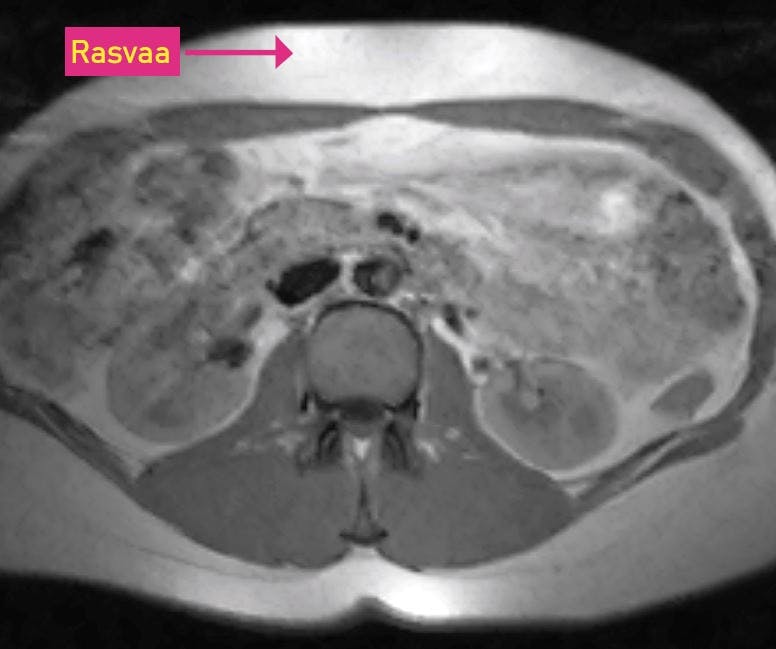

RASVAA SISÄELINTEN VÄLISSÄ Vatsan poikkileikkaus. Kuvassa valkoisena näkyvää rasvaa on sekä välittömästi ihon alla että vatsaontelossa sisäelinten välissä.